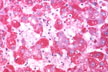

Intracellular and canalicular cholestasis

Fig 58 - INTRACELLULAR AND CANALICULAR CHOLESTASIS: May be present and very prominent i certaincdinsha in tscaefcostti orm of viral hepatitis A.